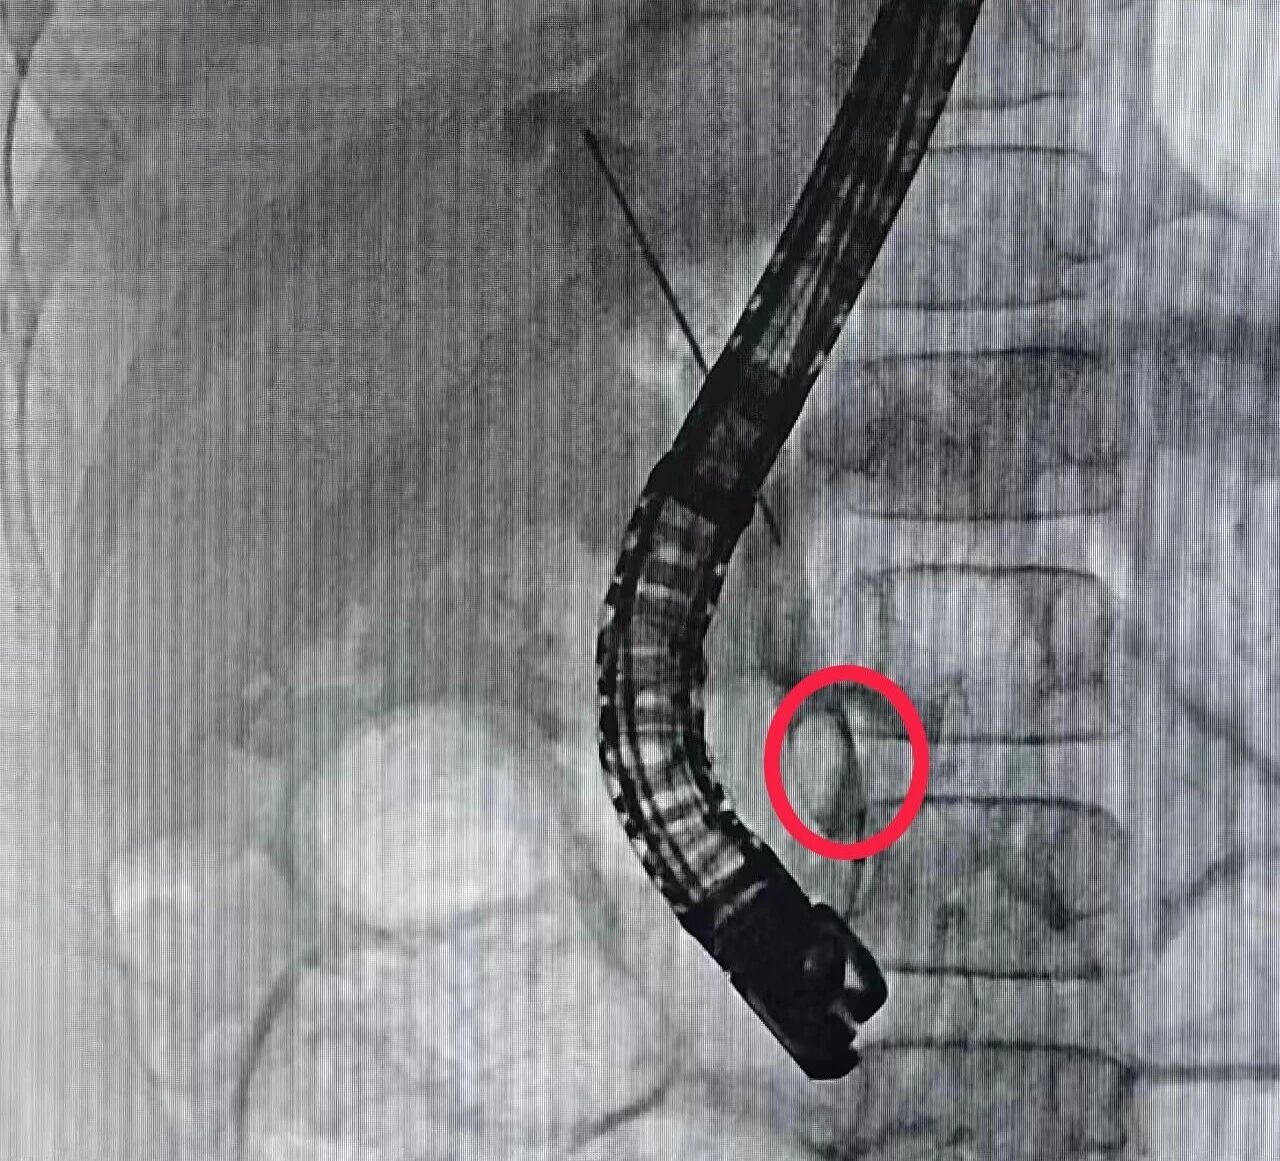

ERCP 是一种微创介入技术,将十二指肠镜插至十二指肠降部,寻找到十二指肠大乳头,从活检管道内插入造影导管至乳头开口处,注入造影剂以显示胰胆管是否存在病变。

手术中,消化内科团队将内窥镜经口腔缓缓置入,精准通过食道、胃部,抵达十二指肠乳头。在 X 光透视的引导下,医生细致地将结石取出,并精准植入两枚微型支架,成功疏通了胆汁和胰液的排出通道。